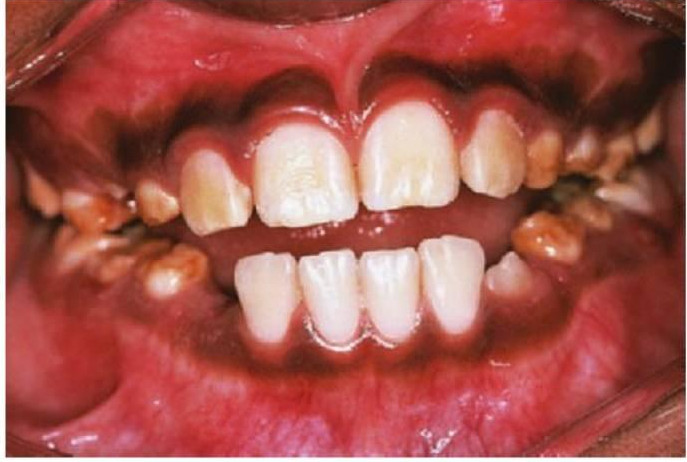

- Pigmentación racial (fig. 8.9).

Enfermedad periodontal en niños

No es infrecuente la presencia de gingivitis en niños, pero la periodontitis con pérdida ósea alveolar suele ser la manifestación de un defecto inmunológico subyacente serio. Dos formas de enfermedad periodontal en niños, la periodontitis prepuberal y la periodontitis juvenil, se asocian a una flora bacteriana característica que incluye Actinobacillus actinomy-cetemcomitans, Prevotella intermedia, Eikenella corrodens y Capnocytophaga sputigena. Se cree que la presencia de estas bacterias está relacionada con una menor resistencia del huésped, sobre todo con la neutropenia o los defectos en la función de los neutrófilos. Los defectos en las células B muestran pocos cambios orales, pero la función alterada de las células T se manifestará con gingivitis, periodontitis y candidiasis graves (fig. 8.17D).